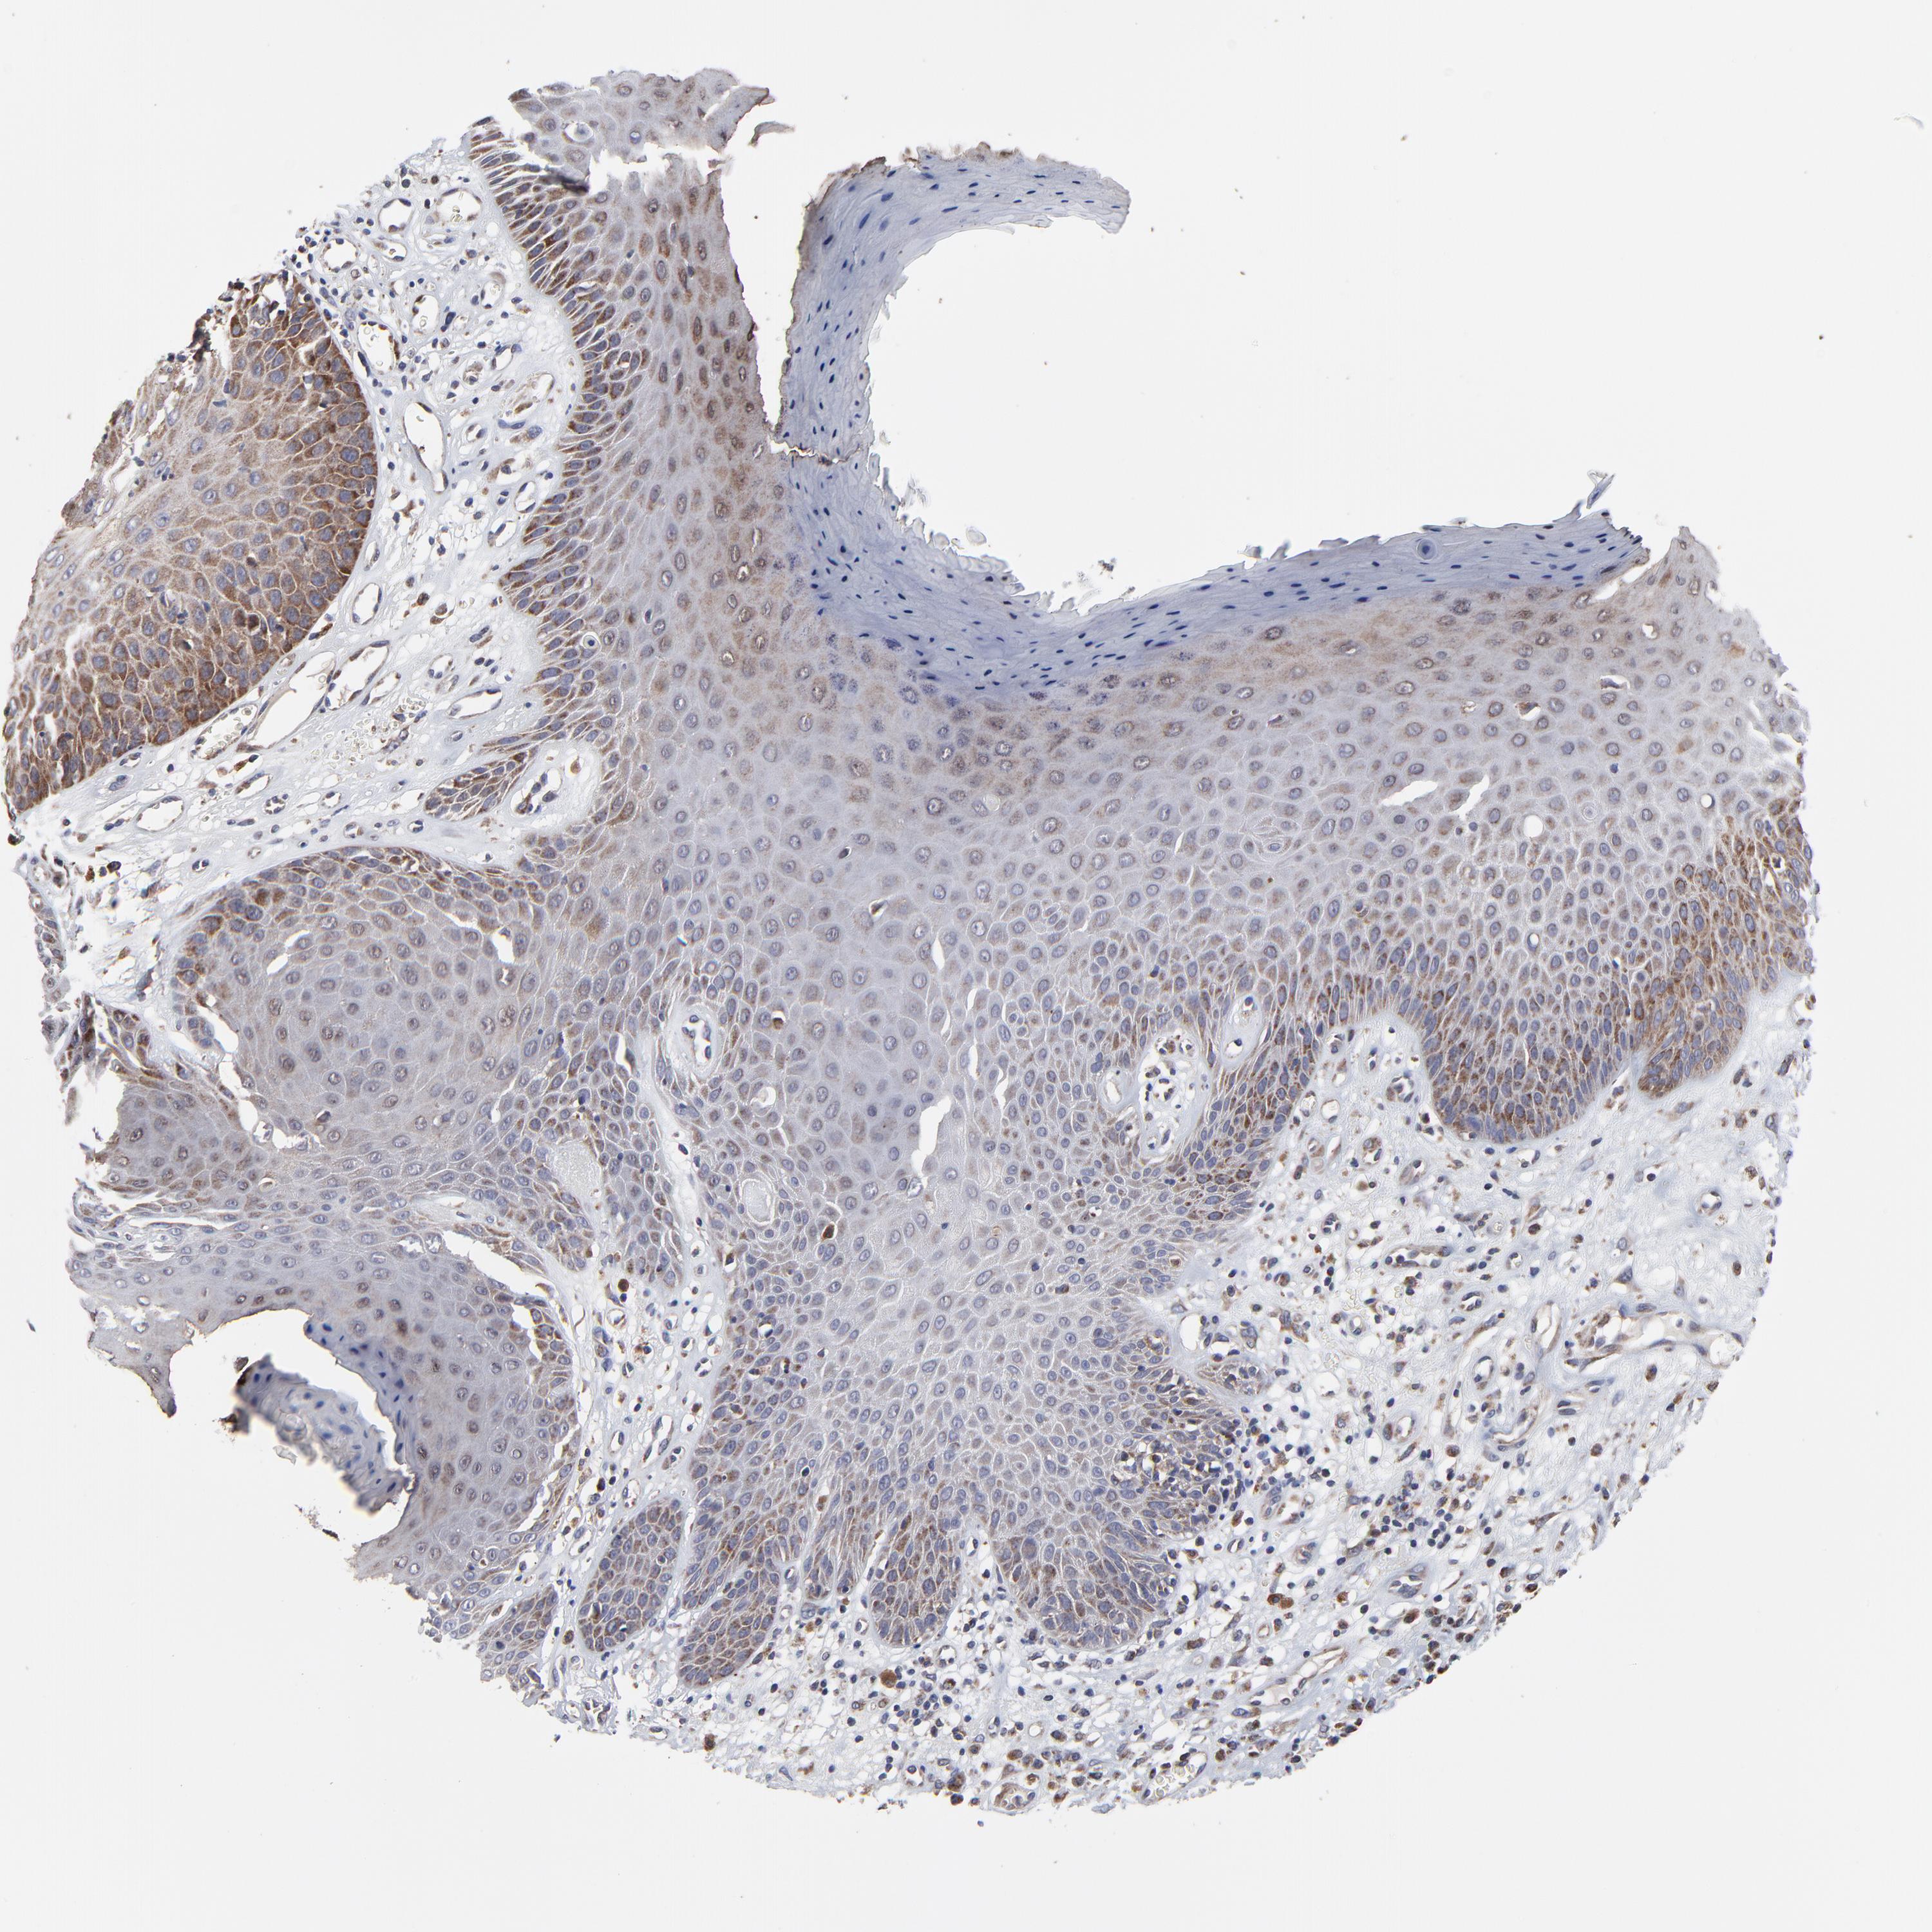

SKIN CANCER - Protein expressioni

A mouse-over function shows sample information and annotation data. Click on an image to view it in a full screen mode. Samples can be filtered based on level of antibody staining by selecting one or several of the following categories: high, medium, low and not detected. The assay and annotation is described here.

Antibody stainingi

Antibody staining in the annotated cell types in the current human tissue is reported as not detected, low, medium, or high, based on conventional immunohistochemistry profiling in selected tissues. This score is based on the combination of the staining intensity and fraction of stained cells.

Each image is clickable and will lead to virtual microscopy that enables deeper exploration of all samples and also displays staining intensity scores, fraction scores and subcellular localization as well as patient and tissue information for each sample.

Antibody HPA003251

Staining

High

Medium

Low

Not detected

Intensity

Strong

Moderate

Weak

Negative

Quantity

>75%

75%-25%

<25%

None

Location

Nuclear

Cytoplasmic/membranous

Cytoplasmic/membranous,nuclear

Squamous cell carcinoma, NOS

Basal cell carcinoma